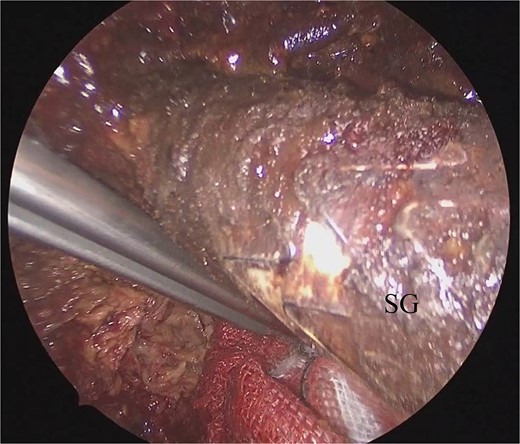

She underwent surgery under general anesthesia. A midline abdominal incision and an intraperitoneal approach were employed. The retroperitoneal space was accessed from the lateral side of the sigmoid colon to reach the CIA. The aneurysm was incised midway. The hematoma and coils were removed, and the stent graft was observed. The laparoscope was utilized to inspect areas obscured from direct view, such as behind the stent graft, to confirm that no type I or IIIb endoleak was present (Fig. 5). A type II endoleak was observed near the proximal neck of the stent graft, which was thought to be the cause of the aneurysm expansion. The IIAA was sutured with 3–0 monofilament, and the aneurysm was closed. The left ureter was close, and care was taken during suturing to avoid including it in the stitches. The operation took 177 min, and the patient was discharged on the tenth day postoperation. Follow-up CT at 7 months postoperation showed a reduction in aneurysm size (Fig. 6).

Laparoscopic view of checking for type I endoleak presence. SG, stent graft.